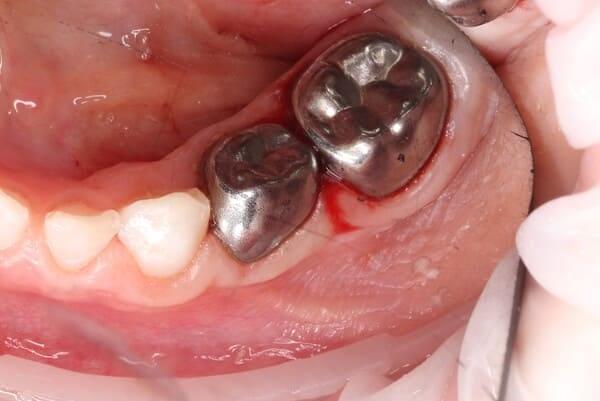

Дівчинка, 5 років. Лікування зворотнього пульпіту тимчасових зубів 85,84 та їх відновлення за допомогою стандартних металевих коронок. Лікування проводилось в умовах закису азоту кисневої седації. Період зміни зубів - 10-12 років.